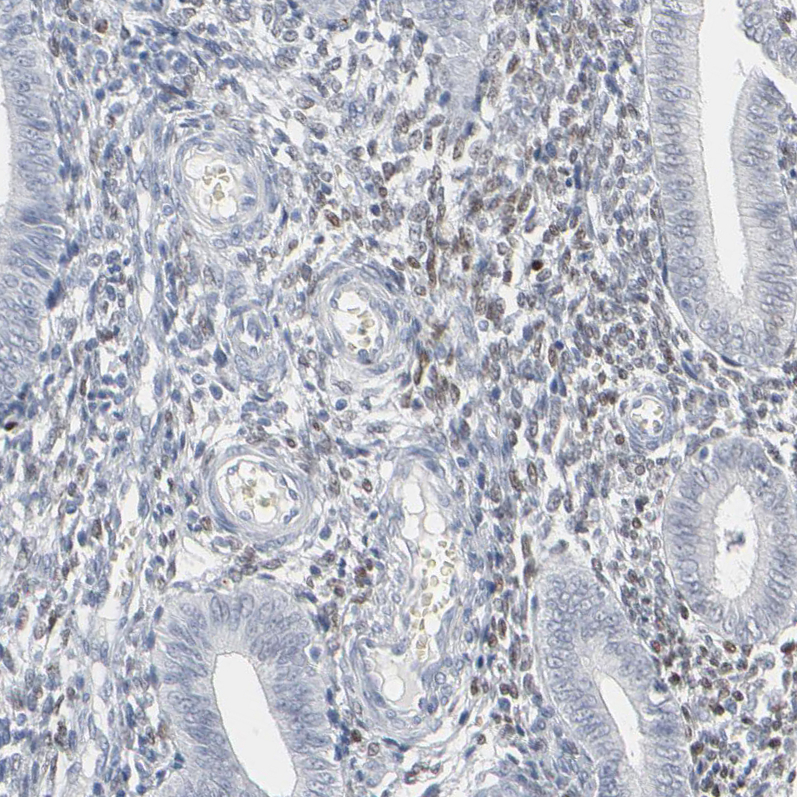

Immunohistochemistry analysis in human skin and pancreas tissues using HPA003259 antibody. Corresponding MITF RNA-seq data are presented for the same tissues.